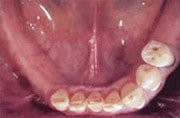

Früher wäre hier nur eine herausnehmbare Teilprothese infrage gekommen.

Fehlen mehrere Zähne, so spricht man vom teilbezahnten Kiefer. Solche größeren Zahnlücken konnten früher oftmals nur mit herausnehmbaren Teilprothesen geschlossen werden, wenn eine Brückenversorgung nicht mehr möglich war. Implantate erlauben, die Lücke mit einer implantatgetragenen festsitzenden Brücke zu schließen, ohne herausnehmbare Prothesen und ohne Abschleifen gesunder Nachbarzähne.

Gestern

herausnehmbare Teilprothese mit Klammern